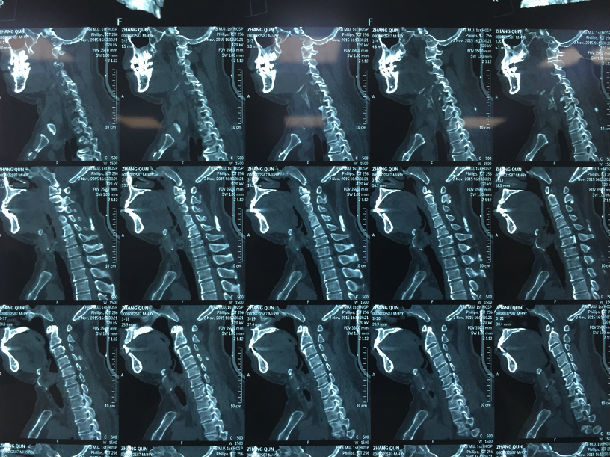

手术前-多节段颈椎间盘突出/黄韧带肥厚/颈椎管狭窄-脊髓损伤

显微镜下经颈后路行单开门椎管扩大成形术-颈椎管明显增宽/脊髓受压解除/患者逐渐康复